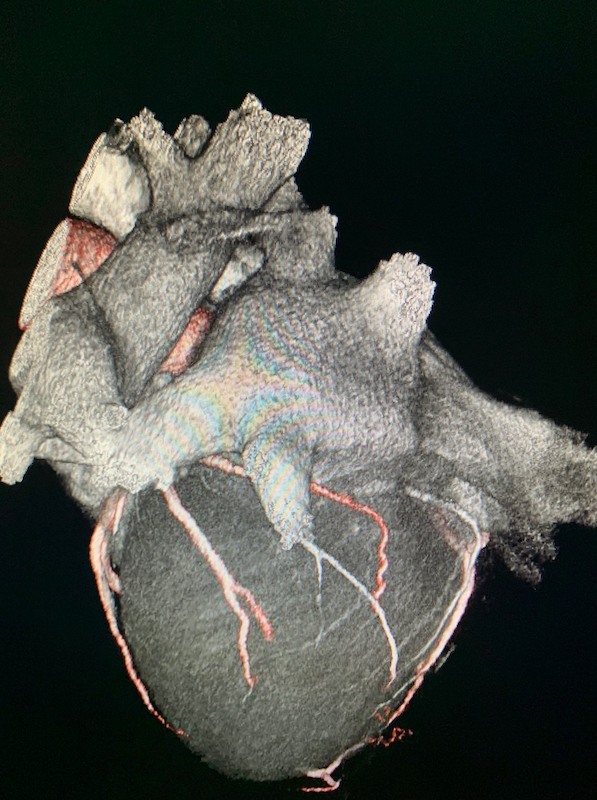

We believe in keeping you as healthy as possible. One of the ways we do this is by checking for heart disease with a Coronary CT Angiogram (CCTA) — a non-invasive scan that can see disease in your heart vessels even if you have no symptoms.

Most people have no symptoms until it’s too late. A Coronary CT Angiogram (CCTA) lets us see disease in the vessels of your heart — before a heart attack happens.

Right coronary scan